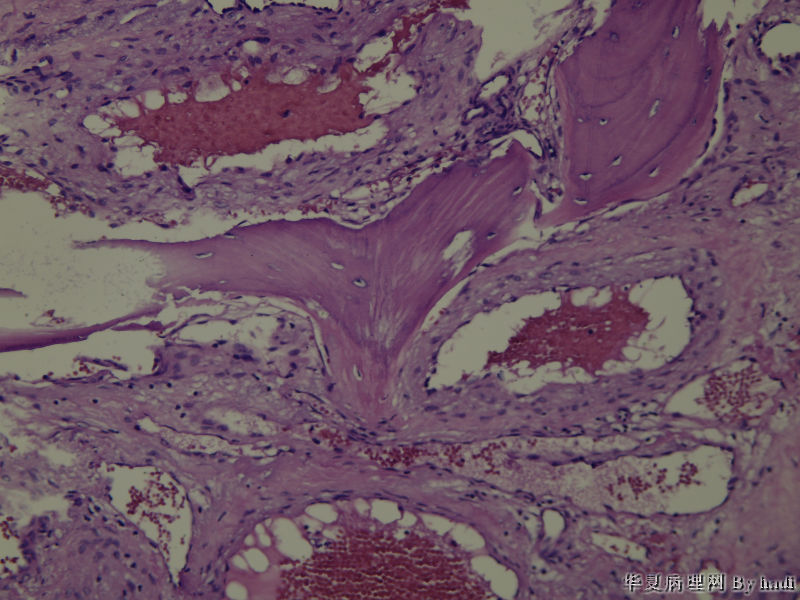

鼻腔肿瘤,成人男性

图2

纤维血管瘤?看不清间质有无异型